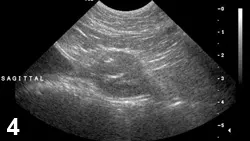

FIGURE 4

Sagittal view of a prostate in a castrated dog. Prostatic mineralization suggests neoplasia.

• Diagnosis of PN can be supported by intraprostatic mineralization and complex parenchymal changes on ultrasonography (Figure 4).

• Prostatic fine-needle aspiration or biopsy can be confirmatory.